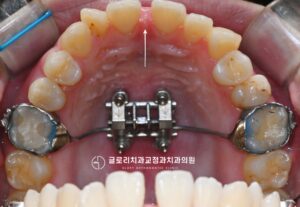

안녕하세요.상봉동 교정치과 김정은 원장입니다. 오늘은 총생과 정중선 편위가 동반된 부정교합을상악골 확장장치를 활용한 비발치 교정으로 치료한 케이스를 소개드리려 합니다. 총생은 치아가 자랄 공간이 부족해 치열이 겹치거나 틀어지는 상태를 말하는데보통 전치부에서 두드러지게…